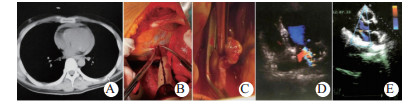

| 图 2 例4紧急剖胸心包减压、心脏修补,剖腹脾切除(A:术前CT示血心包; B、C:心包减压后钳闭左心耳破口; D:术后15 d超声心动图示二尖瓣重度反流; E:术后130 d超声心动图复查示二尖瓣轻度反流) Fig 2 Case 4 having emergency decompression of thoracic pericardium, cardiac repair, and abdominal splenectomy (A: Preoperative CT showed blood pericardium; B and C: Pericardial decompression performed to close the rupture of left auricle; D: Echocardiography showed severe mitral regurgitation on postoperative day 15; E: Echocardiography showed mild mitral regurgitation on postoperative day 130) |

心内结构伤不在急诊手术厘清,术后从体征和影像学诊断后,心功能可代偿者不在急诊期处理。体外循环肝素化可加重多发伤出血; 换瓣术等也易失败[2, 9]。另外笔者观察到与先天性室缺和瓣膜病变不同,损伤较小者有愈合或部分愈合可能,临床症征和影像学均证实(图 2D、E)。因此应待3~6个月无改善后再手术。出现附壁血栓和感染性心内膜炎等并发症应严密观察和处理,急诊期不用抗凝药。心功能失代偿的心内结构伤需提前手术[1, 9, 16]。